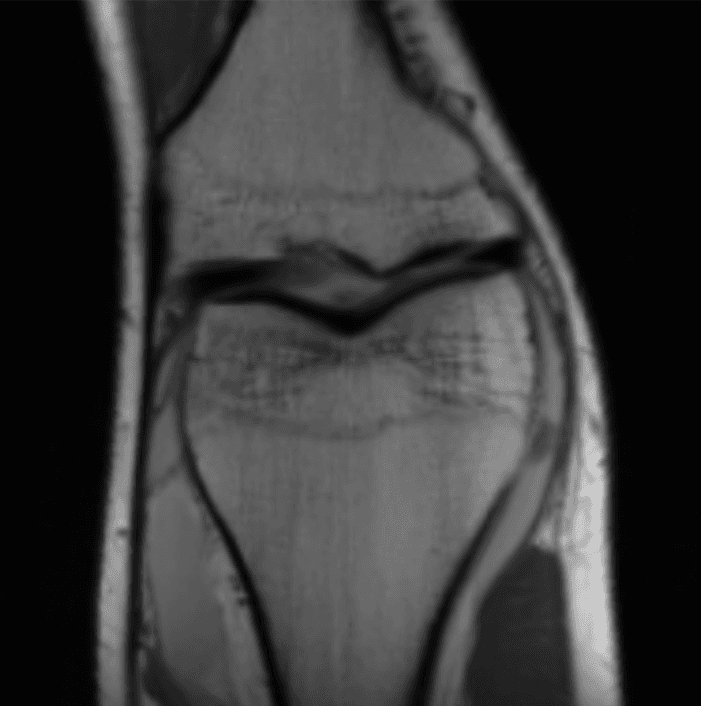

How in the world is this data useful? Image reconstruction is this incredible procedure that can turn this mess of sensor data into an actual image. After doing image reconstruction on the sensor data above, we get:

Now that's much better! (this is an MRI of the knee.) So how does this magical procedure of turning sensor data into images work?